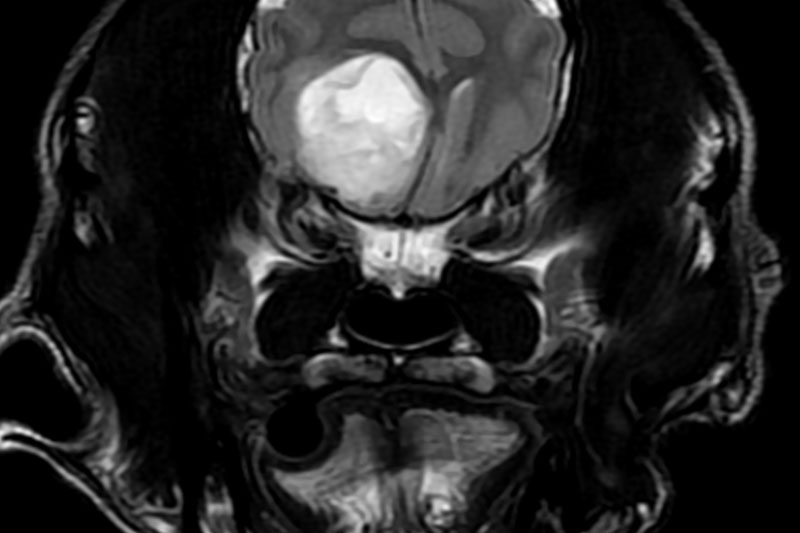

병변의 위치·모양·크기를 정량적으로 분석

AI 자동 보정으로 미세 병변 패턴까지 탐지

신속 판독을 통한 빠른 의사결정 지원

고해상도 영상 확보로 반복 촬영 감소

뇌·척수 등 중추신경계 연부조직 변화 정밀 확인

관절·인대·연골 등 운동계 미세 손상 진단

종양의 경계·성질·침윤 범위 세밀 평가

복부 장기 초기 병변 및 연부조직 이상 분석

혈관 구조·혈류 변화·신경 경로 시각화

수술 전 3D 구조 기반 정밀 수술 계획 수립